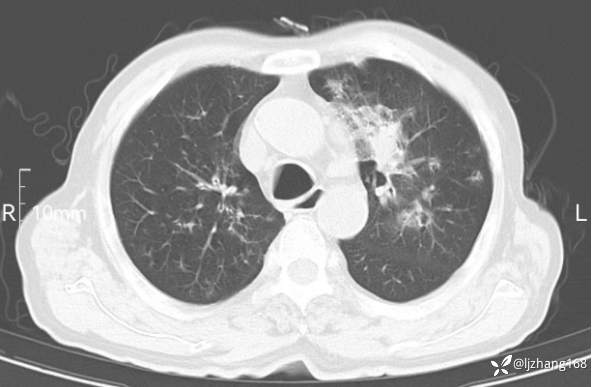

辅助检查:胸部CT:双肺肺气肿,间质性病变,血气分析:PH 7.413, PCO2 29.2mmHg, PO2,81.8mmHg,乳酸 3.3mmol/1,剩余碱-4.0mmol/1,HC03 18.8mmol/1。全血超敏C反应蛋白:超敏C反应蛋白 135.60 mg/L、 白细胞 14x19^9/L,中性粒细胞11.6x10^9/L。